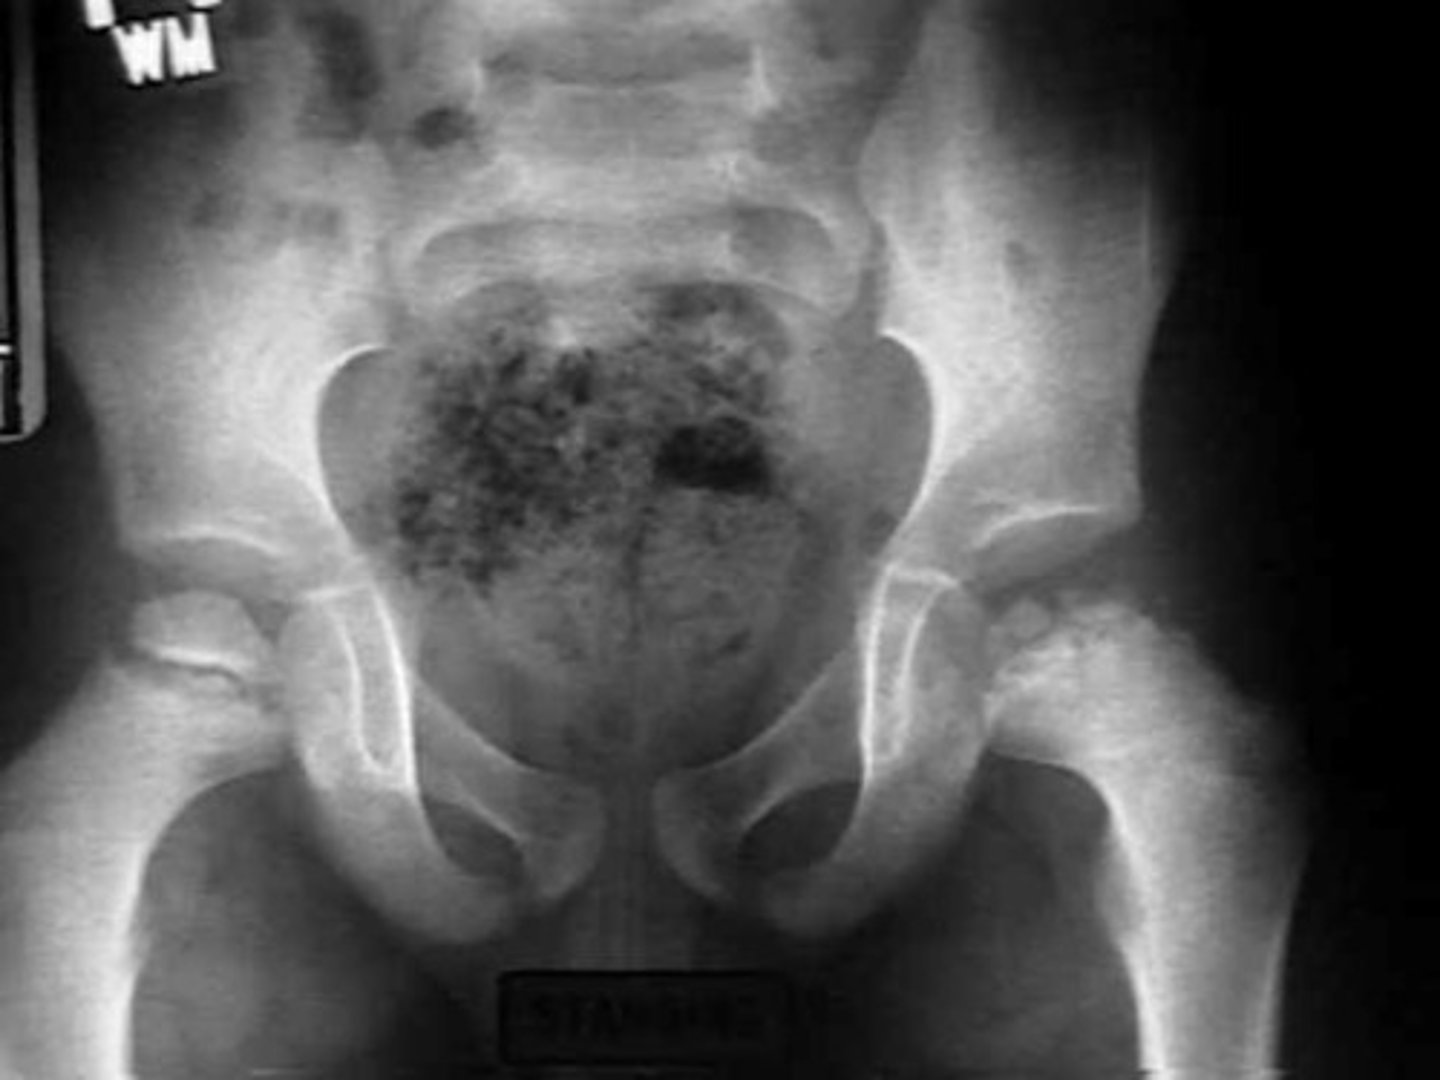

Dx: Premature adrenarche/pubarche, severe cystic acne resistant to tx, accelerate linear growth, advanced bone age, normal electrolytes. Normal testicular volume for age. LH levels low at baseline and do not increase after stimulation w/ GnRH agonist.

Gonadotropin-independent precocious puberty caused by late onset (non classic) congenital adrenal hyperplasia secondary to 21-hydroxylate (CYP21A2) deficiency